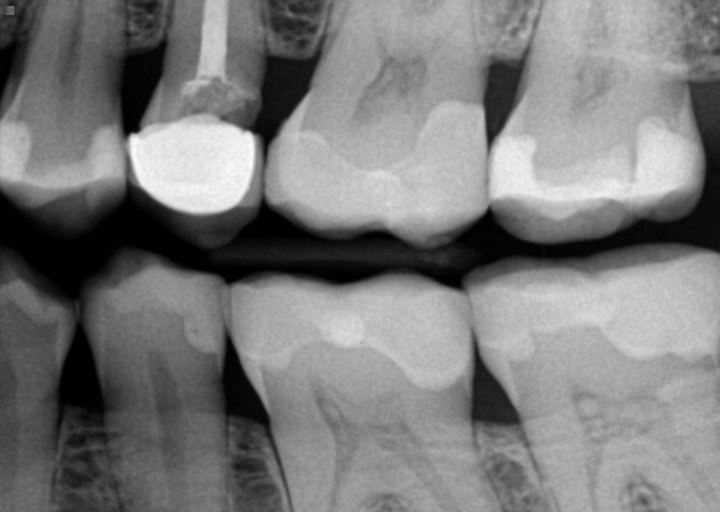

My dentist advised me to have a crown put on a wisdom tooth because it was cracked and food was getting in there. I went in for the intial work, preparation for temporary crown. I paid $1,169 for the initial work of preparing the area, temporary crown and permanent crown a few weeks after. On the intial visit, the dentist said I had a problem with the gums and he had to use the laser treatment to correct it. At that time I was not advised of the cost to do this. After going back for the permanent crown 4 weeks later, I was told that I owed $895, because of the laser surgery that was performed. So, instead of the original quote of $1,300, minus 10% discount, it is now costing me over $2,200. He explained that the laser takes the place of actual gum surgery, it took about 5 minutes, with 3 to 4 laser beams. I would like to know what the usual charge is for this work, I feel as if I have been mistreated. I am on Social Security, just recently signed up for dental insurance, but there is wait of one year for any oral surgery, crowns, etc.Thank you for your anticipated response. Eileen Bannister

Crown lengthening is usually performed when there is not enough tooth structure above the bone level to properly place a crown.  If it is not performed it can lead to periodontal issues and bone loss which can be more costly and painful. The average cost is usually between $450-$600.   If you were not informed prior to the procedure being performed of the cost and did not sign a treatment consent, you cannot be held responsible for the charge.   Even though you have a waiting period on your insurance plan, crown lengthening is considered a periodontal procedure and your insurance has an in network fee that is to be charged.  If the provider is out of network, they are able to charge what they want.  Call your insurance company and inquire the fee that the provider is contracted to charge you. Companies, like Metlife, often include crown lengthening in the crown fee, so there is no additional charges to the patient.  They are not allowed to charge over the insurance fee, even if there is a waiting period.  If you paid with a credit card, you can dispute the charge of the crown lengthening by calling and filing it.